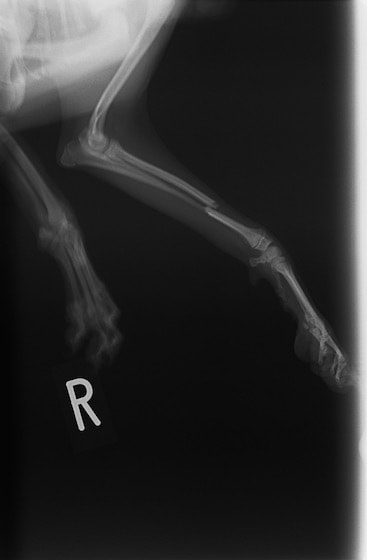

ペルシャ猫 11ヶ月齢 雄

他院にて左大腿骨遠位の成長板骨折(salter-harrisⅠ型)が認められており、治療相談を目的として来院。当院にて、キルシュナーワイヤーを用いたピンニングにより骨折部位の整復を行いました。術後の経過は良好で、現在も経過観察中です。

術前レントゲン